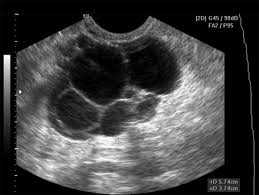

Người bị mắc bệnh buồng trứng đa nang có thể kinh nguyệt ít, ít dần, không đúng chu kỳ, không thấy hiện tượng trứng rụng hằng tháng, kết hôn sau 3 năm vẫn chưa có con. Buồng trứng đa nang có một lớp vỏ dày, chắc và không có sẹo phóng noãn. Nếu không được điều trị, các nang trứng không to lên được, không vỡ được, nằm dưới lớp vỏ dày của buồng trứng. Khi siêu âm, đặc biệt là siêu âm bằng đầu dò qua đường âm đạo, sẽ thấy nhiều nang trứng kích thước dưới 10mm, phân bố như chuỗi hạt đeo cổ nằm ngay lớp vỏ buồng trứng. Phẫu thuật ổ bụng có thể phát hiện thấy vỏ màng bao quanh buồng trứng dày lên, mặt cắt cho thấy có nhiều bọc rỗng với kích thước khác nhau.